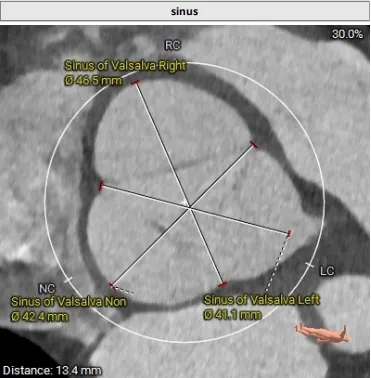

42.4mm&41.1mm&46.5mm

冠脉风险评估

Left Coronary 8.0mm

Right Coronary 18.7mm

左冠开口较低,结合瓦氏窦大小,预估冠脉风险相对较低